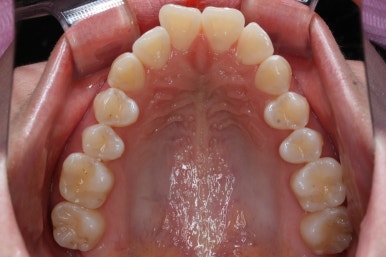

다시 이번 환자분으로 돌아가, 입 안모습을 보시겠습니다.

부산무턱교정 키다리아저씨치과에서 처음 내원하셨을 당시의 입 안의 모습입니다.

아래턱이 작아서 상대적으로 윗니들이 많이 돌출되었고, 뻐드러져 있습니다. 윗니들이 배열되어 있는 형태도 V자에 가깝게 입천장이 좁은 양상입니다.

얼굴모습과 입 안의 모습을 모두 고려하여 발치교정을 하기로 하였습니다.

결국 앞니를 뒤로 집어 넣어야 여러 가지가 해결이 되는데, 앞니를 뒤로 넣으려면 자리가 필요하고, 발치를 선택할 수 밖에 없는 상황이었습니다.

다만, 아랫니까지 뽑기에는 적절치 않아서 윗니만 발치하고 진행하기로 하였습니다.